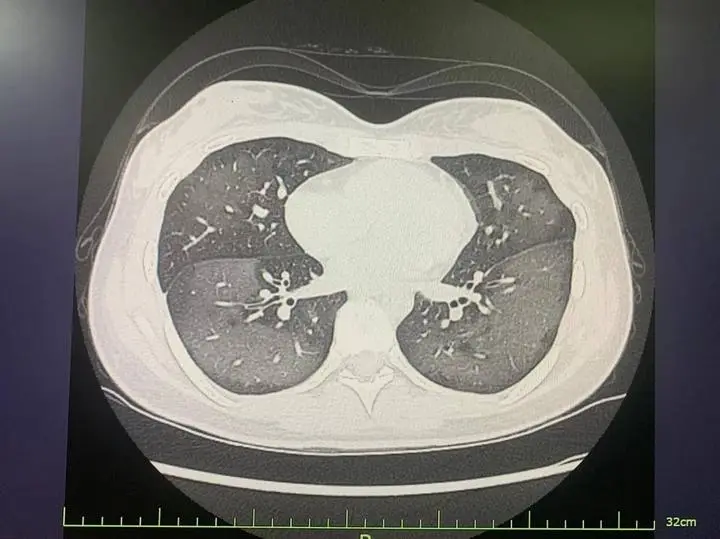

患者肺部CT

据悉,女孩出门前,一边和妈妈说话,一边对着脸和脖子大面积喷射防晒喷雾,没有屏住呼吸。结果刚喷完就咳嗽不止,而且越咳越凶。一个小时过去,她感觉越来越不舒服、呼吸也越来越困难,于是前往就医。经CT检查发现,她的双肺呈现大范围白色样病变,报告提示“白肺”,她被诊断为“急性过敏性肺炎”。